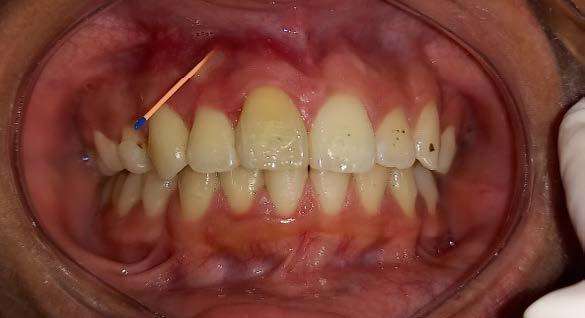

El AOF Sn1 logró el avance mandibular, expansión programada, armonización de arcadas y regularización de la curva de Spee, entonces se determina cambiar dicho aparato por unas PIPS, clase I para mantener el espacio que corresponde a los O.D. 35 y 45, ya que fueron indicadas para extracción los O.D. 75 y 85, esperando la erupción de premolares para terminar el anclaje. Las indicaciones para el paciente fueron uso continuo de las PIPS por 3 meses, solo retirándose para comer e higienizar, revisiones mensuales en la clínica para activación y desgastes de los mantenedores de espacio, vigilando la erupción de los premolares. Posteriormente se indicó su uso nocturno por 4 meses más para mantener estabilidad de los resultados obtenidos.

Después de 18 meses de tratamiento con ortopedia funcional de los maxilares, podemos hacer una comparativa de los resultados obtenidos.

Figura 6. Fotos intraorales antes y después del tratamiento. A. VF B. VL derecha, C. VL izquierda, después de 18 meses de tratamiento D. VF, E. VL derecha, F. VL izquierda.

Al observar las imágenes en el antes y el después podemos concluir que se previenen y se bloquea el avance de la maloclusión dental y esquelética clase II división 2 en el paciente, de esta manera se previenen tratamientos más invasivos y complejos